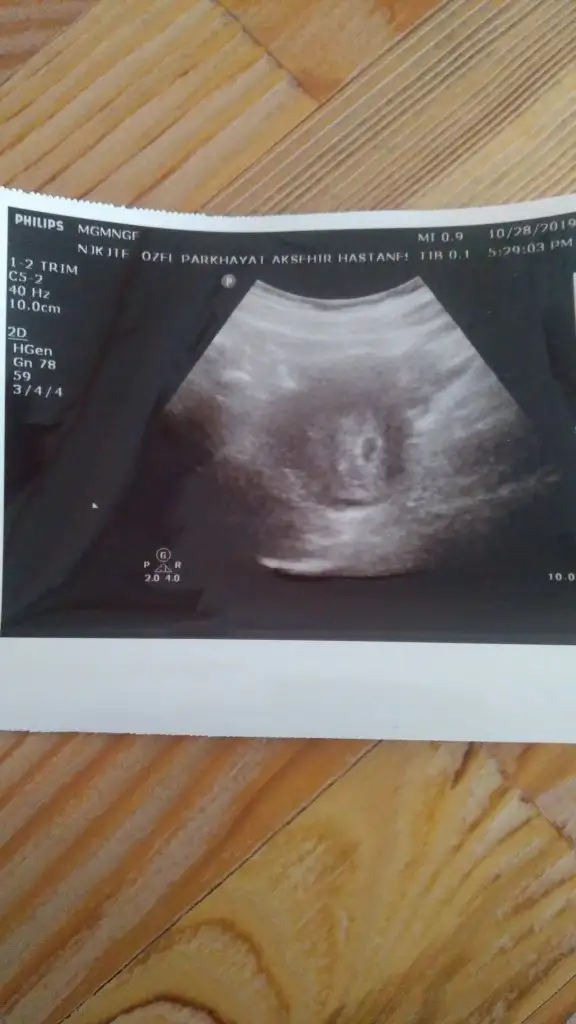

Eklentiler

• IMG_20191028_100845.webp

IMG_20191028_100845.webp

24,4 KB · Görüntüleme: 60